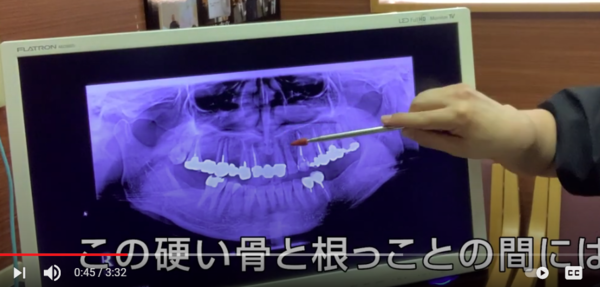

レントゲン写真は硬いものが白くうつります。

↑

ここに白い線がはっきりくっきりと

うつっています。

ここには

硬い骨

太い骨

があるのです。

ではこの硬い骨、太い骨は

どういう役目があるのか?

この硬い骨と太い骨は

口の部屋と鼻の部屋が混ざらないように

仕切っている壁なんですね。

口側には

歯の頭と歯の根っこと

その根っこを支える骨が

あります。

硬い骨と根っこの間には隙間(骨)があります。